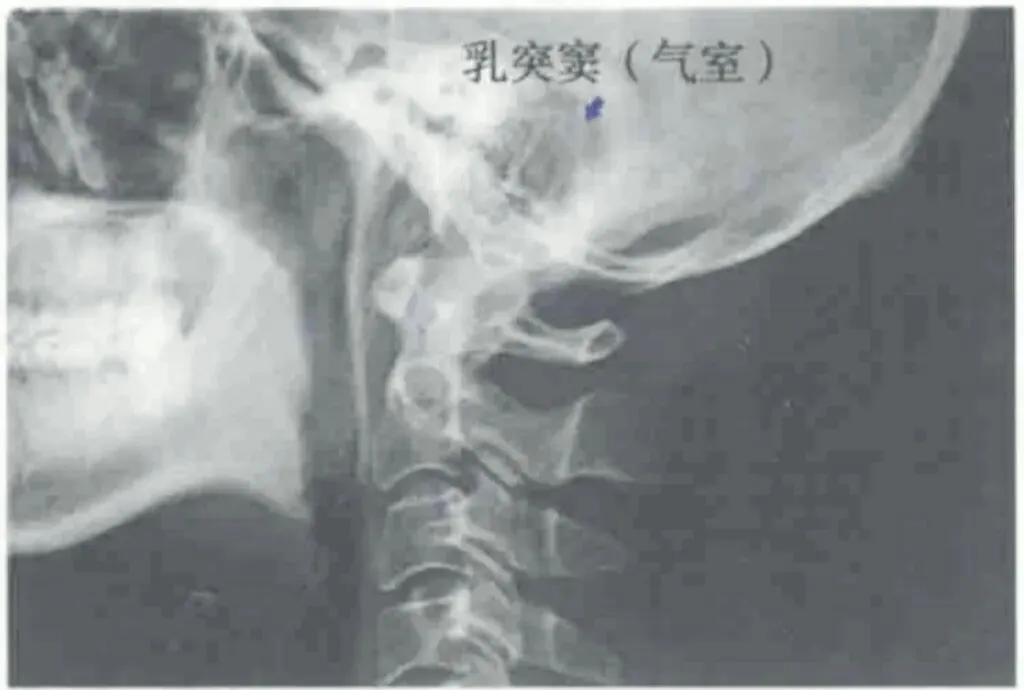

头夹肌、胸锁乳突肌、头最长肌长期兴奋紧张,其附着处骨膜张力增高,乳突窦静脉回流障碍,导致乳突窦炎性水肿,刺激其中走行的神经,出现多种症状

如无菌性炎症刺激面神经,引起面肌痉挛,通过放松头夹肌、胸锁乳突肌、头最长肌或去掉引起上述肌肉张力增加的因素,对面肌痉挛有积极治疗作用;刺激锁骨肌神经引起耳鸣;刺激鼓索神经引起舌根部麻刺感及流涎;刺激岩大神经引起流泪、流涕。